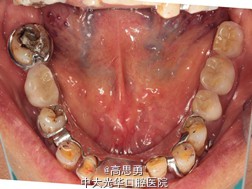

5、试戴支架 检查支架的就位、固位可,无翘动,调HE,抛光,用蜡堤取颌位关系,上颌架,排牙,比色C4。

6、试排牙 检查义齿的就位、固位可,无翘动,观察人工牙的咬合状况,尖窝接触良好,正中颌位能重复,患者无诉不适,面容自然,外观满意。送加工厂充胶制作最终修复体。

7、试戴 检查义齿的就位、固位可,无翘动,咬合关系正确,利用咬合纸检查,上下颌尖窝接触均匀全面,抛光,患者表示满意,嘱注意事项,定期复诊。